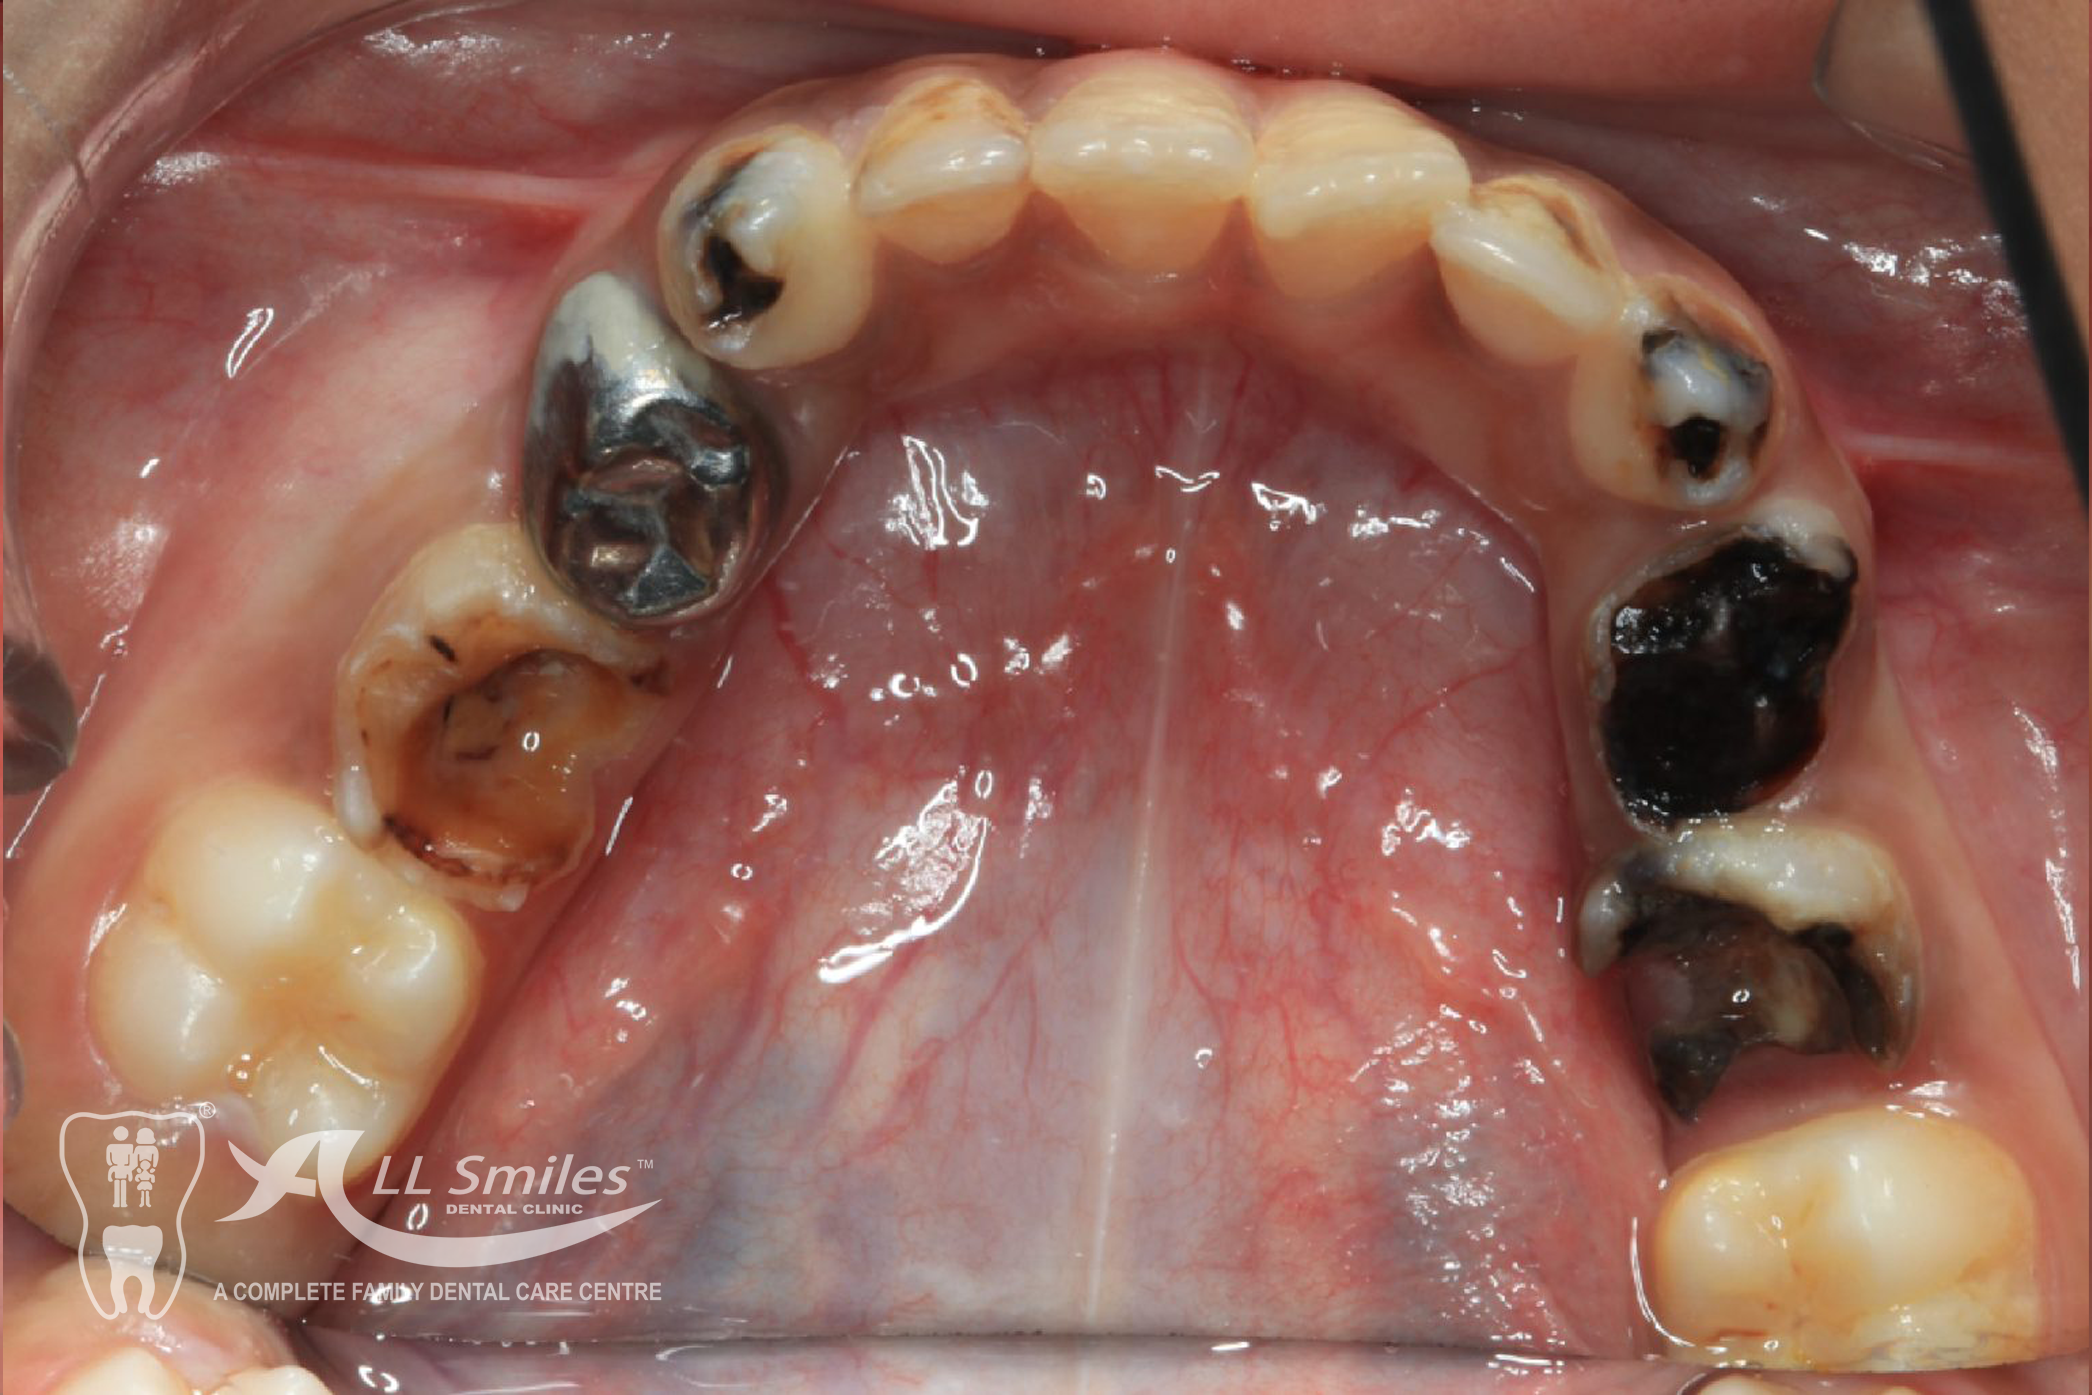

If a child has a cavity, the dentist will remove the decayed portion of the tooth and fill the space with a dental filling. Fillings can be made of various materials, such as composite resin or glass ionomer, depending on the specific needs of the child.

These are treatments performed on baby teeth to save them from extensive decay or infection.

Crowns are tooth-shaped caps that cover and protect damaged or weakened teeth. They are commonly used for baby teeth that have extensive decay or are at risk of fracture.

Child Dentistry Gallery